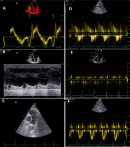

Diagnostic assessment: laboratory investigations on admission revealed a normal complete blood count with white blood cells at 6470 cells/mm3 (normal 4000-10000/mm3), hemoglobin at 12.7 g/dL (normal for women 12-16 g/dl), and platelet count at 176000 cells /mm3 (normal 150000-400000/mm3). Coagulation studies showed a prothrombin time of 99% with an activated partial thromboplastin time ratio of 1.00. Notably, fibrinogen was decreased at 1.8 g/L (normal 2-4 g/L). D-dimers were markedly elevated at 11.63 mg/L. Renal function was normal with creatinine at 4.95 mg/L (normal for women 5.07-11.1 mg/L) and urea at 0.32 g/L (normal 0.15-0.45 g/L). Liver enzymes were within normal limits: AST at 22 U/L (normal 5-34 U/L), ALT at 14 U/L (normal 0-55 U/L) with a normal serum lipase level of 12 UI/l (normal < 60U/l). Creatine kinase was mildly elevated at 256 U/L (normal for women 29-168 UI/l). C-reactive protein was normal at 3.93 mg/L (normal 0-5 mg/L). High-sensitivity troponin was within normal limits at 1.9 ng/L (<26 ng/l), and NT-proBNP was at 29.7 pg/mL. The electrocardiogram showed no abnormalities (Figure 1) and the chest X-ray was unremarkable with no infiltrates, pleural effusion, or cardiomegaly. Transthoracic echocardiography showed a non-dilated right ventricle with good systolic function. There was no paradoxical septal motion, right ventricular pressure overload, signs of pulmonary hypertension, or any other echocardiographic evidence of acute cor pulmonale. No visible thrombus was detected in the pulmonary artery. The left ventricle was non-dilated with good systolic function (ejection fraction of 60%) and left ventricular filling pressures were normal (Figure 2). Given the respiratory symptoms and markedly elevated D-dimers, a computed tomography pulmonary angiography (CTPA) was performed, which revealed segmental pulmonary embolism in the right posterobasal segment and left lower lobe without signs of right ventricular strain (Figure 3). Lower limb venous doppler ultrasound did not reveal any deep vein thrombosis. An etiological workup was performed to rule out underlying malignancy. Cerebral CT angiography and cervico-thoraco-abdomino-pelvic contrast-enhanced CT scans showed no abnormalities, and tumor markers were negative. A formal thrombophilia screening was not performed, as this was a first episode of venous thromboembolism clearly linked to a temporary and identifiable risk factor.

Figure 2: transthoracic echocardiography demonstrating normal right ventricular function without signs of pulmonary hypertension or right heart strain; A) right ventricular systolic function assessment: tissue Doppler imaging showing normal S wave velocity (0.11 m/s) and M-mode demonstrating normal TAPSE (1.9 cm); B) parasternal short-axis view showing normal pulmonary artery trunk diameter without evidence of thrombus; C) Doppler assessment of pulmonary pressures: pulmonary insufficiency flow; D) tricuspid regurgitation jet; E), and pulmonary artery acceleration time; F) demonstrating absence of pulmonary hypertension